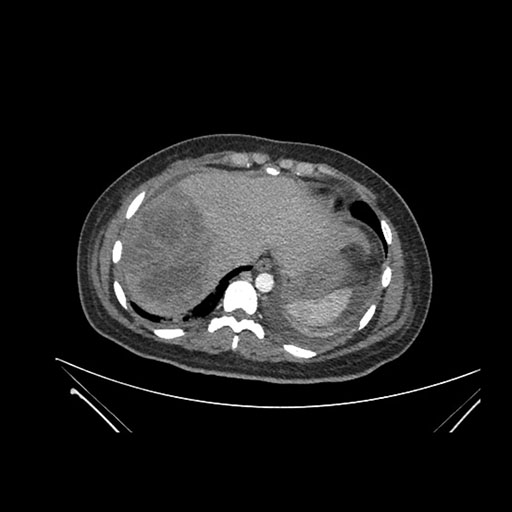

Imaging Analysis

Look through the patient's CT scan to identify any areas of concern for the necessary procedure.

Axial Arterial

Based on initial findings, which issue(s) would you be most concerned about?